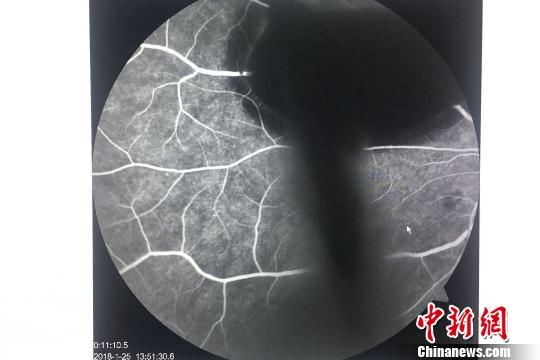

小潘的眼底荧光造影检查图,亮色纹路为眼底血管,右上黑影为血块?!≈有馈∩?/div>

在成都华厦眼科医院,经医生详细检查,发现小潘竟然是罕见的“瓦尔萨尔瓦视网膜病变”引起的眼底出血,其左眼中的“黑影”正是眼底血管破裂渗出的血液。